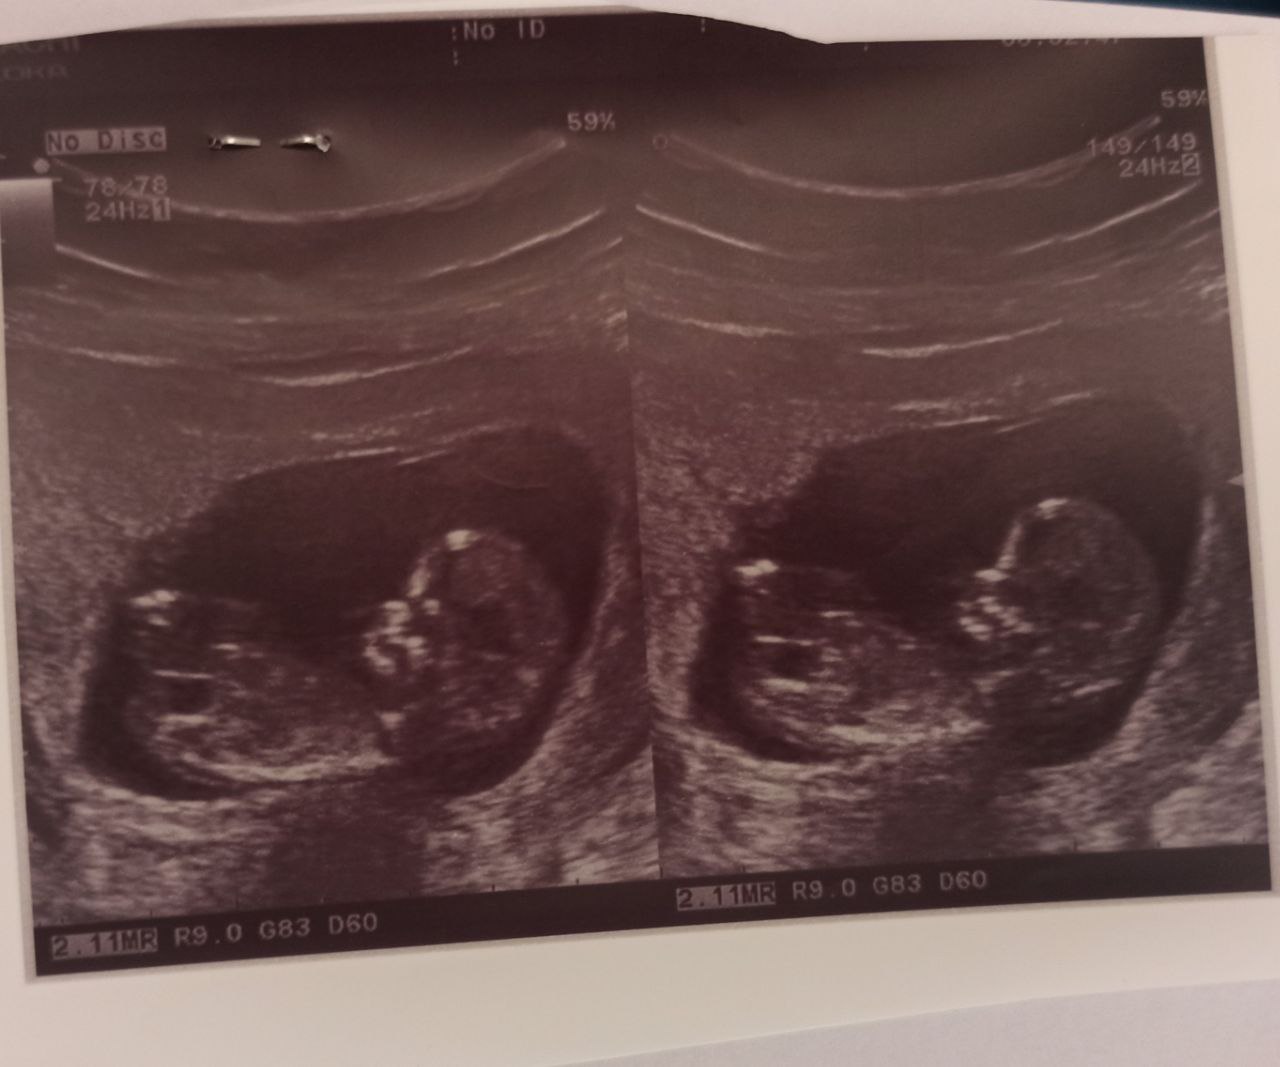

roomoo عضویت: 1398/12/05 تعداد پست: 2589 اره گلم سونو ان تی احتمال نداد؟ تماشا کردن شغل دوم اکثر ماهاست؛البته اگر قضاوت کردن را شغل اول مان حساب کنید